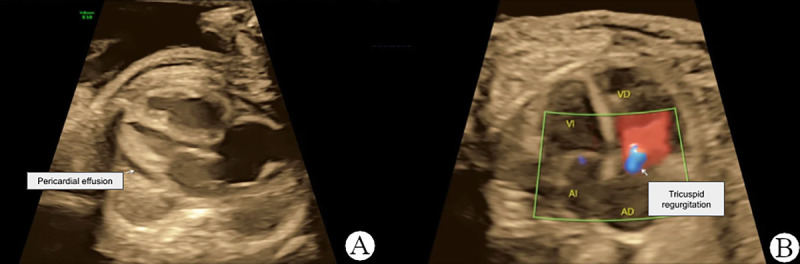

Approximately 75% of lymphangiomas manifest in the head and neck region, with limb and bone involvement observed in only 2% of cases. This case report presents a rare instance of fetal lymphangioma associated with hydrops fetalis, affecting the left lower extremity and abdomen. A 22-year-old secundigravida woman was referred to the gynecology department at 31.2 weeks of gestation. Initial fetal ultrasound revealed a live fetus with a large lymphangioma involving the left lower extremity, gluteal region, and abdomen. Additional ultrasound findings included subcutaneous edema, pericardial effusion, ascites, placentomegaly, and tricuspid regurgitation. Postnatal clinical examination confirmed the diagnosis of lymphatic malformation. Notably, only one other similar case has been reported in the English-language PubMed database. This report adds to the medical literature as a rare instance of prenatally diagnosed lymphangioma-associated hydrops fetalis.

约75%的淋巴管瘤表现在头颈部,仅2%的病例累及肢体和骨骼。本病例报告提出一个罕见的胎儿淋巴管瘤合并胎儿水肿,影响左下肢和腹部。一名22岁的二次妊娠妇女在妊娠31.2周时被转介到妇科。最初的胎儿超声显示一个活的胎儿,有一个大的淋巴管瘤累及左下肢、臀区和腹部。其他超声表现包括皮下水肿、心包积液、腹水、胎盘肿大和三尖瓣反流。产后临床检查确诊为淋巴畸形。值得注意的是,在英文PubMed数据库中,只有一个类似的病例被报道过。本报告增加了一个罕见的产前诊断淋巴管瘤相关积水胎儿的医学文献。